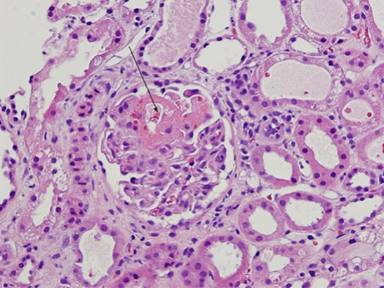

Figure 3. Segmental glomerular necrosis. |

Figure 4. Severe acute tubular necrosis. Note segmental glomerular necrosis (arrow). H&E. |

My patient had an ANCA negative pauci-immune necrotizing glomerulonephritis (thought to be induced by levamisole contaminated cocaine). Initially presented as an acute pancreatitis; this is atypical and rare making the diagnostic process challenging. Pauci-immune necrotizing glomerulonephritis is the most frequent cause of rapidly progressive glomerulonephritis and in 60% of cases. It is associated with positive anti-neutrophil cytoplasmic antibodies (ANCA). It is either the renal manifestation of Wegener’s granulomatosis, microscopic polyangiitis, Churg-Strauss syndrome, or a renal-limited vasculitis. Immune conditions like systemic lupus erythematosus, polyarteritis nodosa and Wegener’s granulomatosis have been reported to rarely cause pancreatitis although few case reports cite Wegener’s granulomatosis affecting the gastrointestinal system with an initial presentation of pancreatitis which may be rapidly progressive and fatal [3]. Although my patient consumed alcohol which may be etiologically tied to pancreatitis, his clinical presentation was very atypical and as his vasculitic picture became clearer, we had to go searching for another etiology of his pancreatitis.